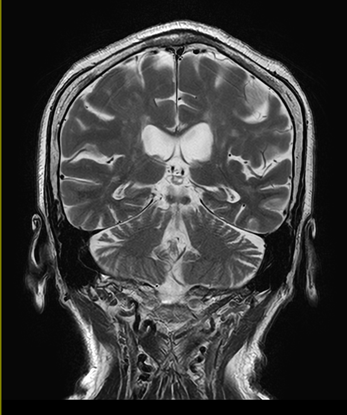

MRI検査

MRIは強力な磁場を利用し、コントラストの高い断層画像をさまざまな方向から画像化する検査です。